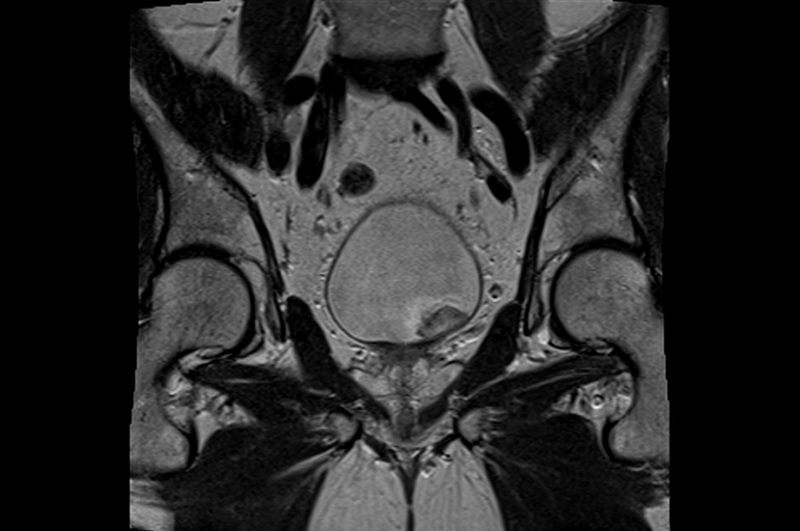

КТ малого таза у женщин - это рентгенологическое исследование на базе протокола сканирования КТ органов малого таза. Фокусом данного обследования становятся: матка, яичники, влагалище, мочевой пузырь, нижние части мочеточников, прямая кишка. Следует сказать, что компьютерная томография малого таза даже на низкодозных томографах сопряжена с лучевой нагрузкой на организм женщины. В среднем доза облучения составляет 7-14 мЗв за одно исследование. Поэтому проводить данную диагностику лучше всего по назначению врача при наличии серьезных медицинских показаний. Если пациентка сама решила в качестве профилактики сделать скрининговое обследование, начать диагностику следует с более безопасной МРТ органов малого таза или более доступного УЗИ.